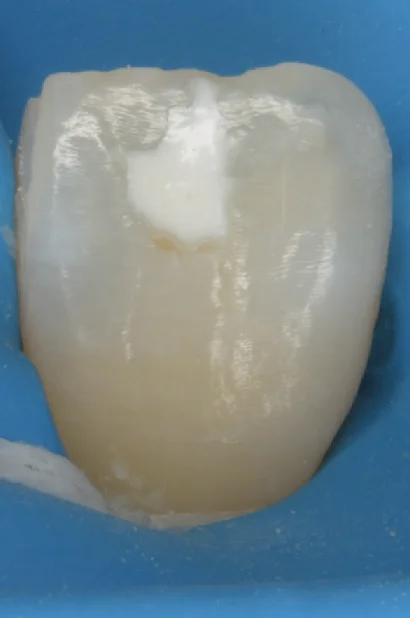

こんな感じで、歯の表面に白い点があることってありませんか?

この部分をホワイトスポットと言います。

こちらがICONにて処置を行った直後の写真になります。

大分薄くはなっていますが、それでもうっすらと残存しているのがわかると思います。